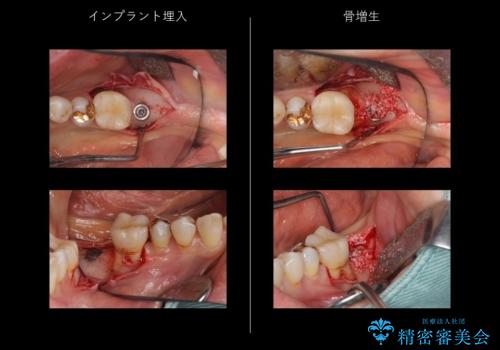

- 半分残していた奥歯の虫歯の状態が良くない為、抜歯をしてインプラントをしました。

歯肉移植時には静脈内鎮静法を併用し、手術時の不安を軽減しました。

- 69.4万円 内訳:左下7(ストローマンインプラント24.2万円 インプラント用仮歯2.2万円 骨増成5.5万円 カスタムアバットメント11万円 FGG(遊離歯肉移植術)11万円 静脈内鎮静5.5万円)費用は治療当時の料金となります

歯肉移植を行うと、炎症に強く歯周病になりにくい歯周組織の状態でのインプラント補綴が可能になります。

他の歯の治療もあり治療に時間をかけることが問題なかった点、また、審美領域ではない点、患者様が時間をかけてもいいのでお手入れしやすく長持ちするインプラントを希望していたことから2回法を選択しております。一回法のメリットは今回は特にありませんでした。患者様のご希望もふまえ、無理せず抜歯後しっかり骨ができるのを待って、角化歯肉を増やすため歯肉移植も行いました。